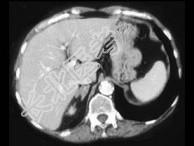

- 单项选择题女,42岁, 夜尿增多伴高血压,实验室检查: 血和尿醛固酮水平增加,请结合图像, 选择最佳答案 ( )

A、双侧肾上腺增生

B、双侧肾上腺腺瘤

C、双侧肾上腺未见异常

D、双侧肾上腺转移瘤

E、双侧肾上腺淋巴瘤